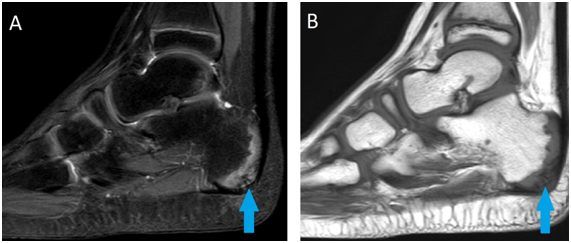

8 years-old boy with pain in the heel of both feet for three months. The pain started when they started to play basketball. Deny traumas and surgeries. Indicates pain at local palpation and walking. MRI demonstrated irregularity of calcaneal apophysis with important edema, corresponding to Sever's disease, with discrete edema of surrounding subcutaneous tissue, in both feet (Figure 1) (Figure 2).

Figure 2 Sagittal MRI of the left foot in T2 SPIR sequence in A and T1 sequence in B demonstrating irregularity of calcaneal apophysis with important edema, corresponding to Sever's disease (blue arrow).